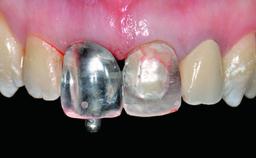

Replacement of a Failing Upper Left Central Incisor: Immediate Placement of an RC Bone Level Implant and Provisionalization

Loading Protocol Immediate

Provisional Implant-Supported Prosthesis Prosthodontic margin < 3 mm apical to mucosal margin Prosthodontic margin < 3 mm apical to mucosal margin